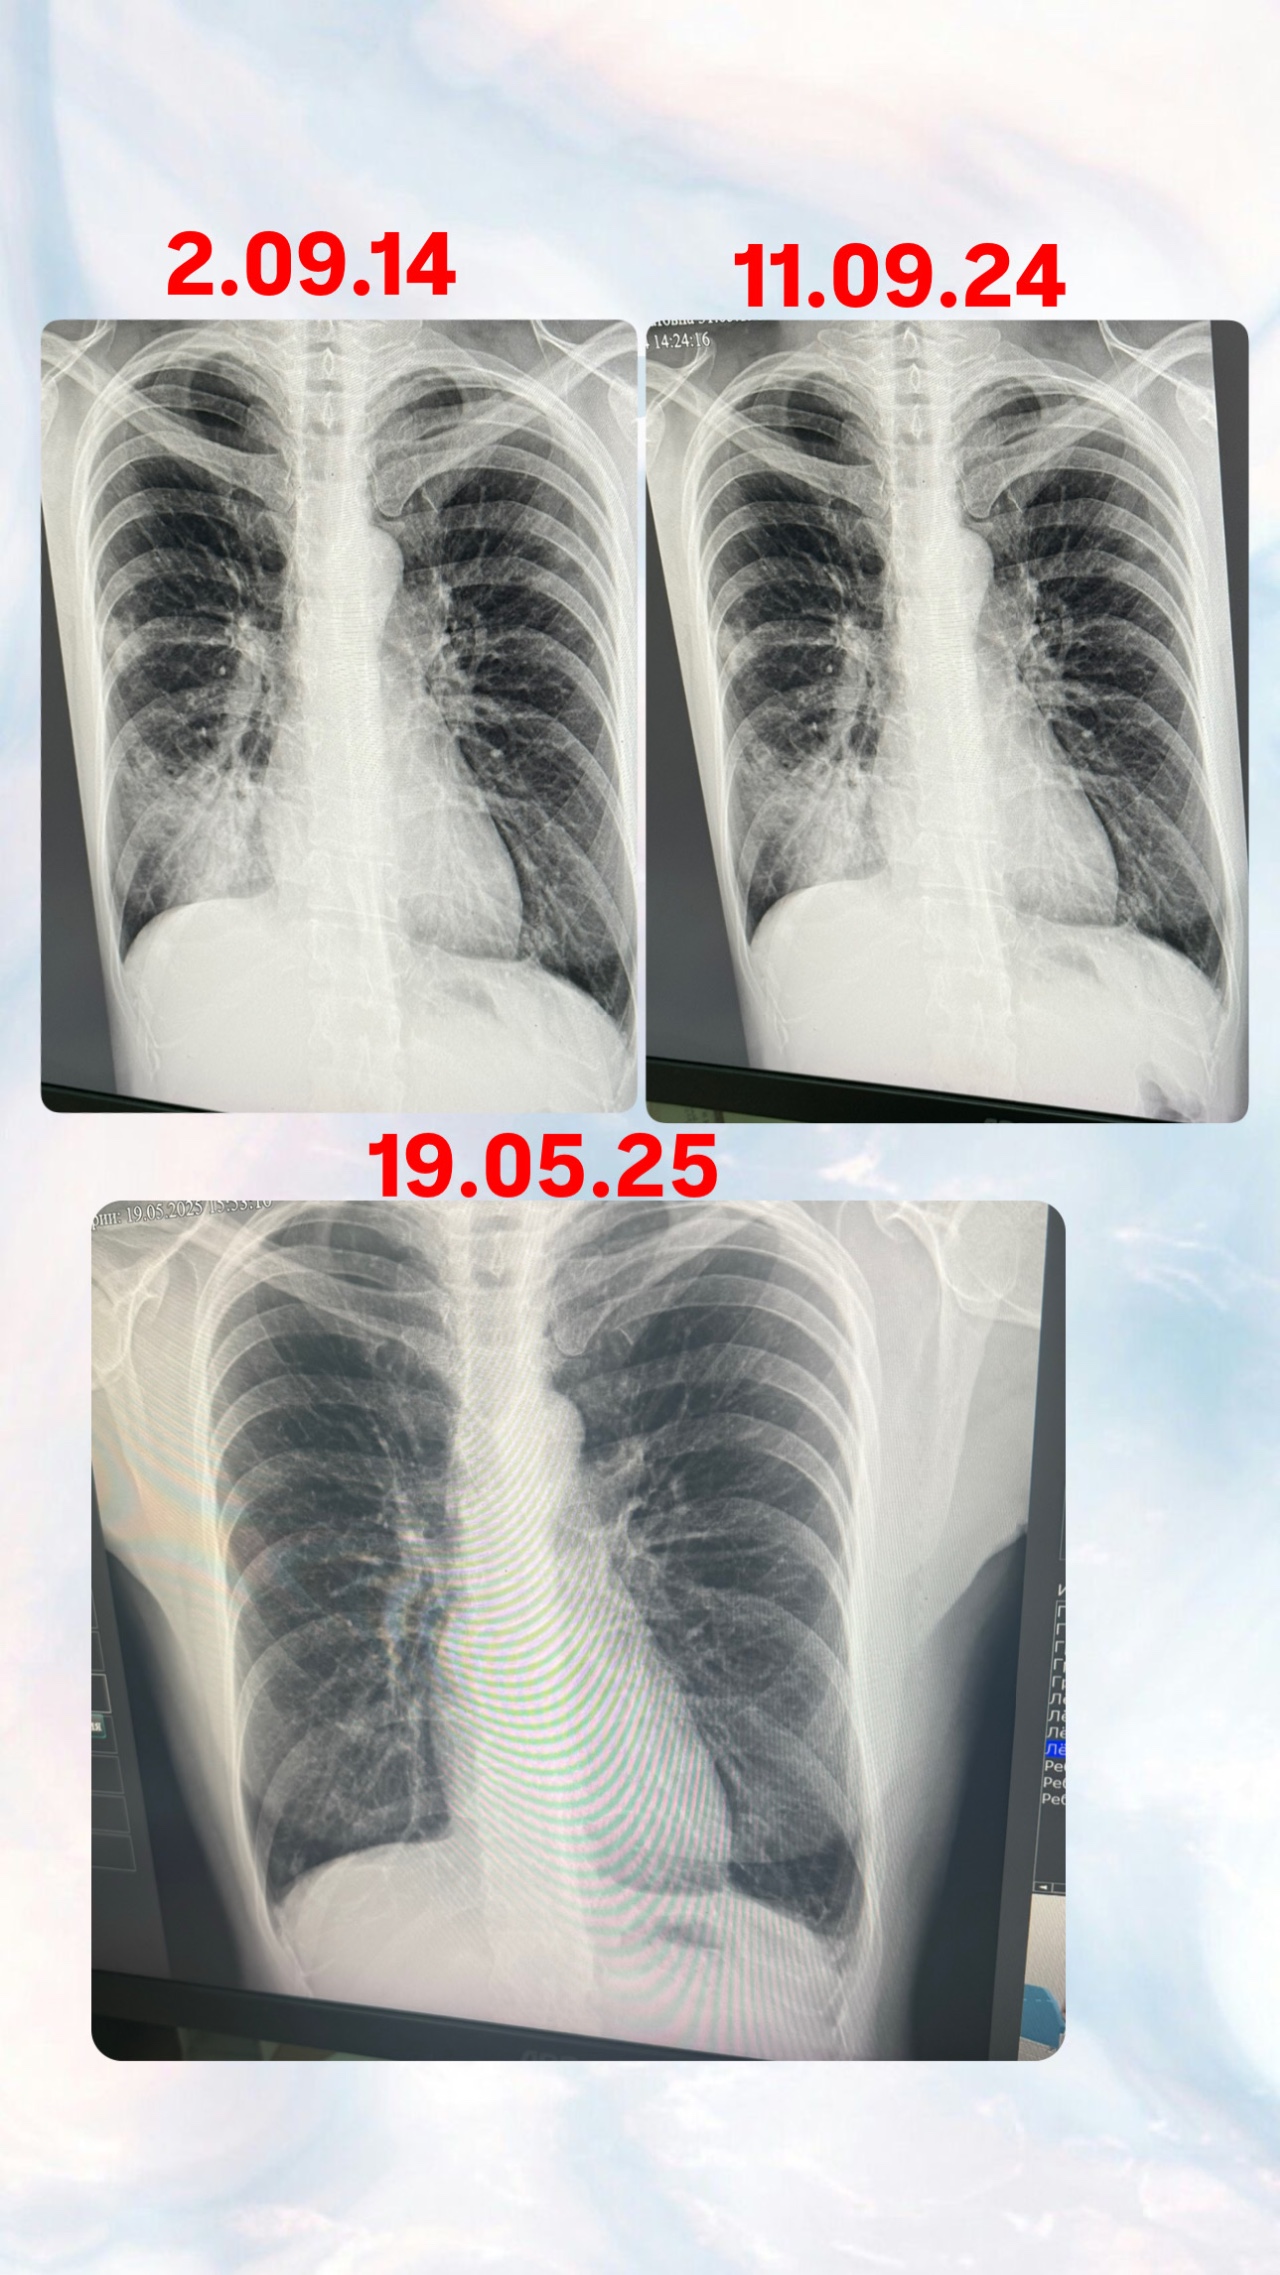

Доброго времени суток! В сентябре 2024 года я переболела пневмонии, температура долго держалась, лежала в больнице 2 недели, повторила рентген снимок в мае 2025 года, посмотрите пожалуйста и дайте свой комментарий, спасибо заранее ????????

Здравствуйте! На представленном снимке признаков пневмонии нет. Отмечаются эмфизематознве изменения верхних отделов, локальный фиброз справа. Надо видеть предыдущие снимки, стоит сделать спирография с пробой на 400 мкг сальбутамола для исключения астмы или ХОБЛ

Динамика положительная пневмония полностью разрешилась Спирография нужна, также необходима вакцинация от пневмококка

Да, совпадает. Постпневмонический фиброз не относится к смертельным заболеваниям и не требует лечения. После любой травмы или большого воспаления остается рубец, это нормально, это законно и это физиологично. Вы же не лечите рубец на руке после пореза через 2 недели после того как рубец затянул рану.

Есть смысл в поддержании противовирусного и антибактериального иммунитета в виде пневмококковой и противогриппозной вакцин. Необходимо пить не менее 1.5 литров воды в день, неплохо работает тонзилгон в плане восстановления слизистой бронхов и легких после воспаления.